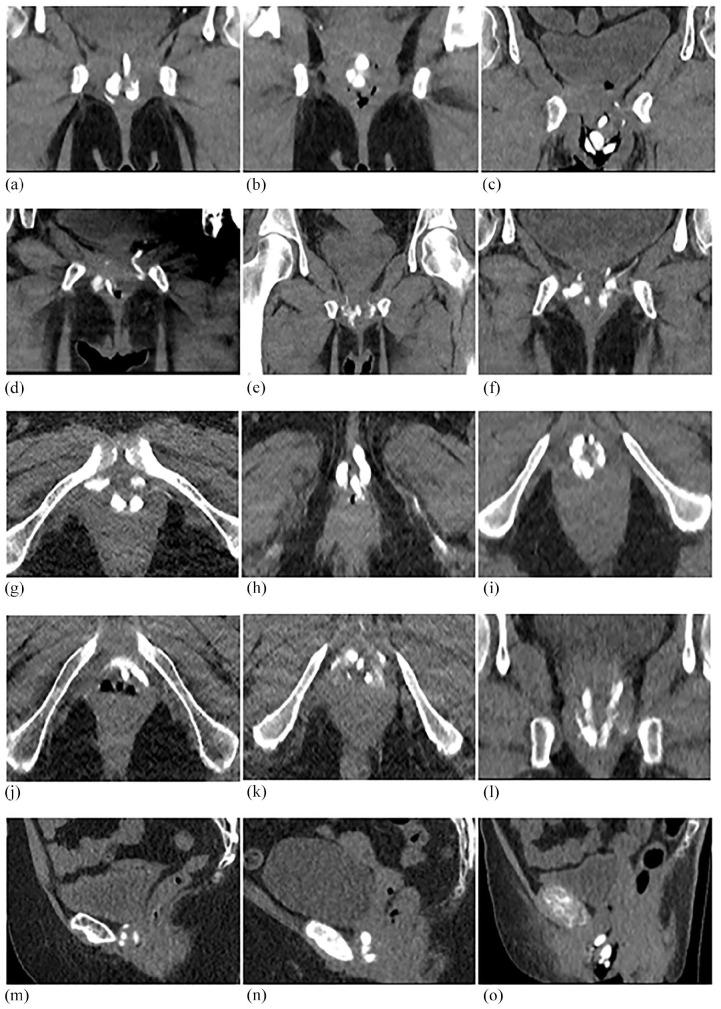

Imaging findings of vinyl dimethyl polydimethylsiloxane used as a paraurethral injectable for female stress urinary incontinence.

Vinyl dimethyl polydimethylsiloxane (VDPDMS) is a urethral bulking agent used for female stress urinary incontinence (SUI), that is clearly visible on computed tomography (CT). Clinical effects are promising, but it remains difficult to identify factors predicting clinical success. Clinical outcome might depend on the shape and position of the implants after injection. Objective of this study is to analyze the appearance and position of bulk material on CT scans and to see whether it is delivered the intended circumferential and mid-urethral position.

A single-center retrospective study was performed in 20 women, treated with VDPDMS for SUI. A senior radiologist analyzed all CTs, using an assessment scheme. This scheme describes whether the bulk is scattered, mid-urethral, and/or circumferentially distributed. The imaging findings were subsequently correlated to the patient global impression of improvement (PGI-I) and the percentage of subjective improvement experienced 6 weeks post-operatively.

The patient's mean age was 61 years, and they underwent median 2.0 previous surgical treatments for SUI. Three patients reported no improvement, 9 patients had 20-90% improvement and 8 reported >90% improvement of their SUI. In 17/74 (24%) positions, the implant was scattered rather than spherical. In 9/20 (45%), the implants were not located in the intended mid-urethral position. In 8/20 patients (40%), the material was distributed circumferentially.

This is the first study describing the position and shape of VDPDMS in patients after treatment. The appearance and position of the implants appears to be variable, but optimal positioning or shape seems to be no absolute requisite for success.